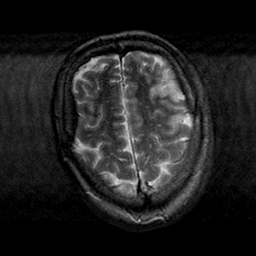

Subacute Stroke, overlay -- Slice #21

[Home][Help][Clinical] Slice 21